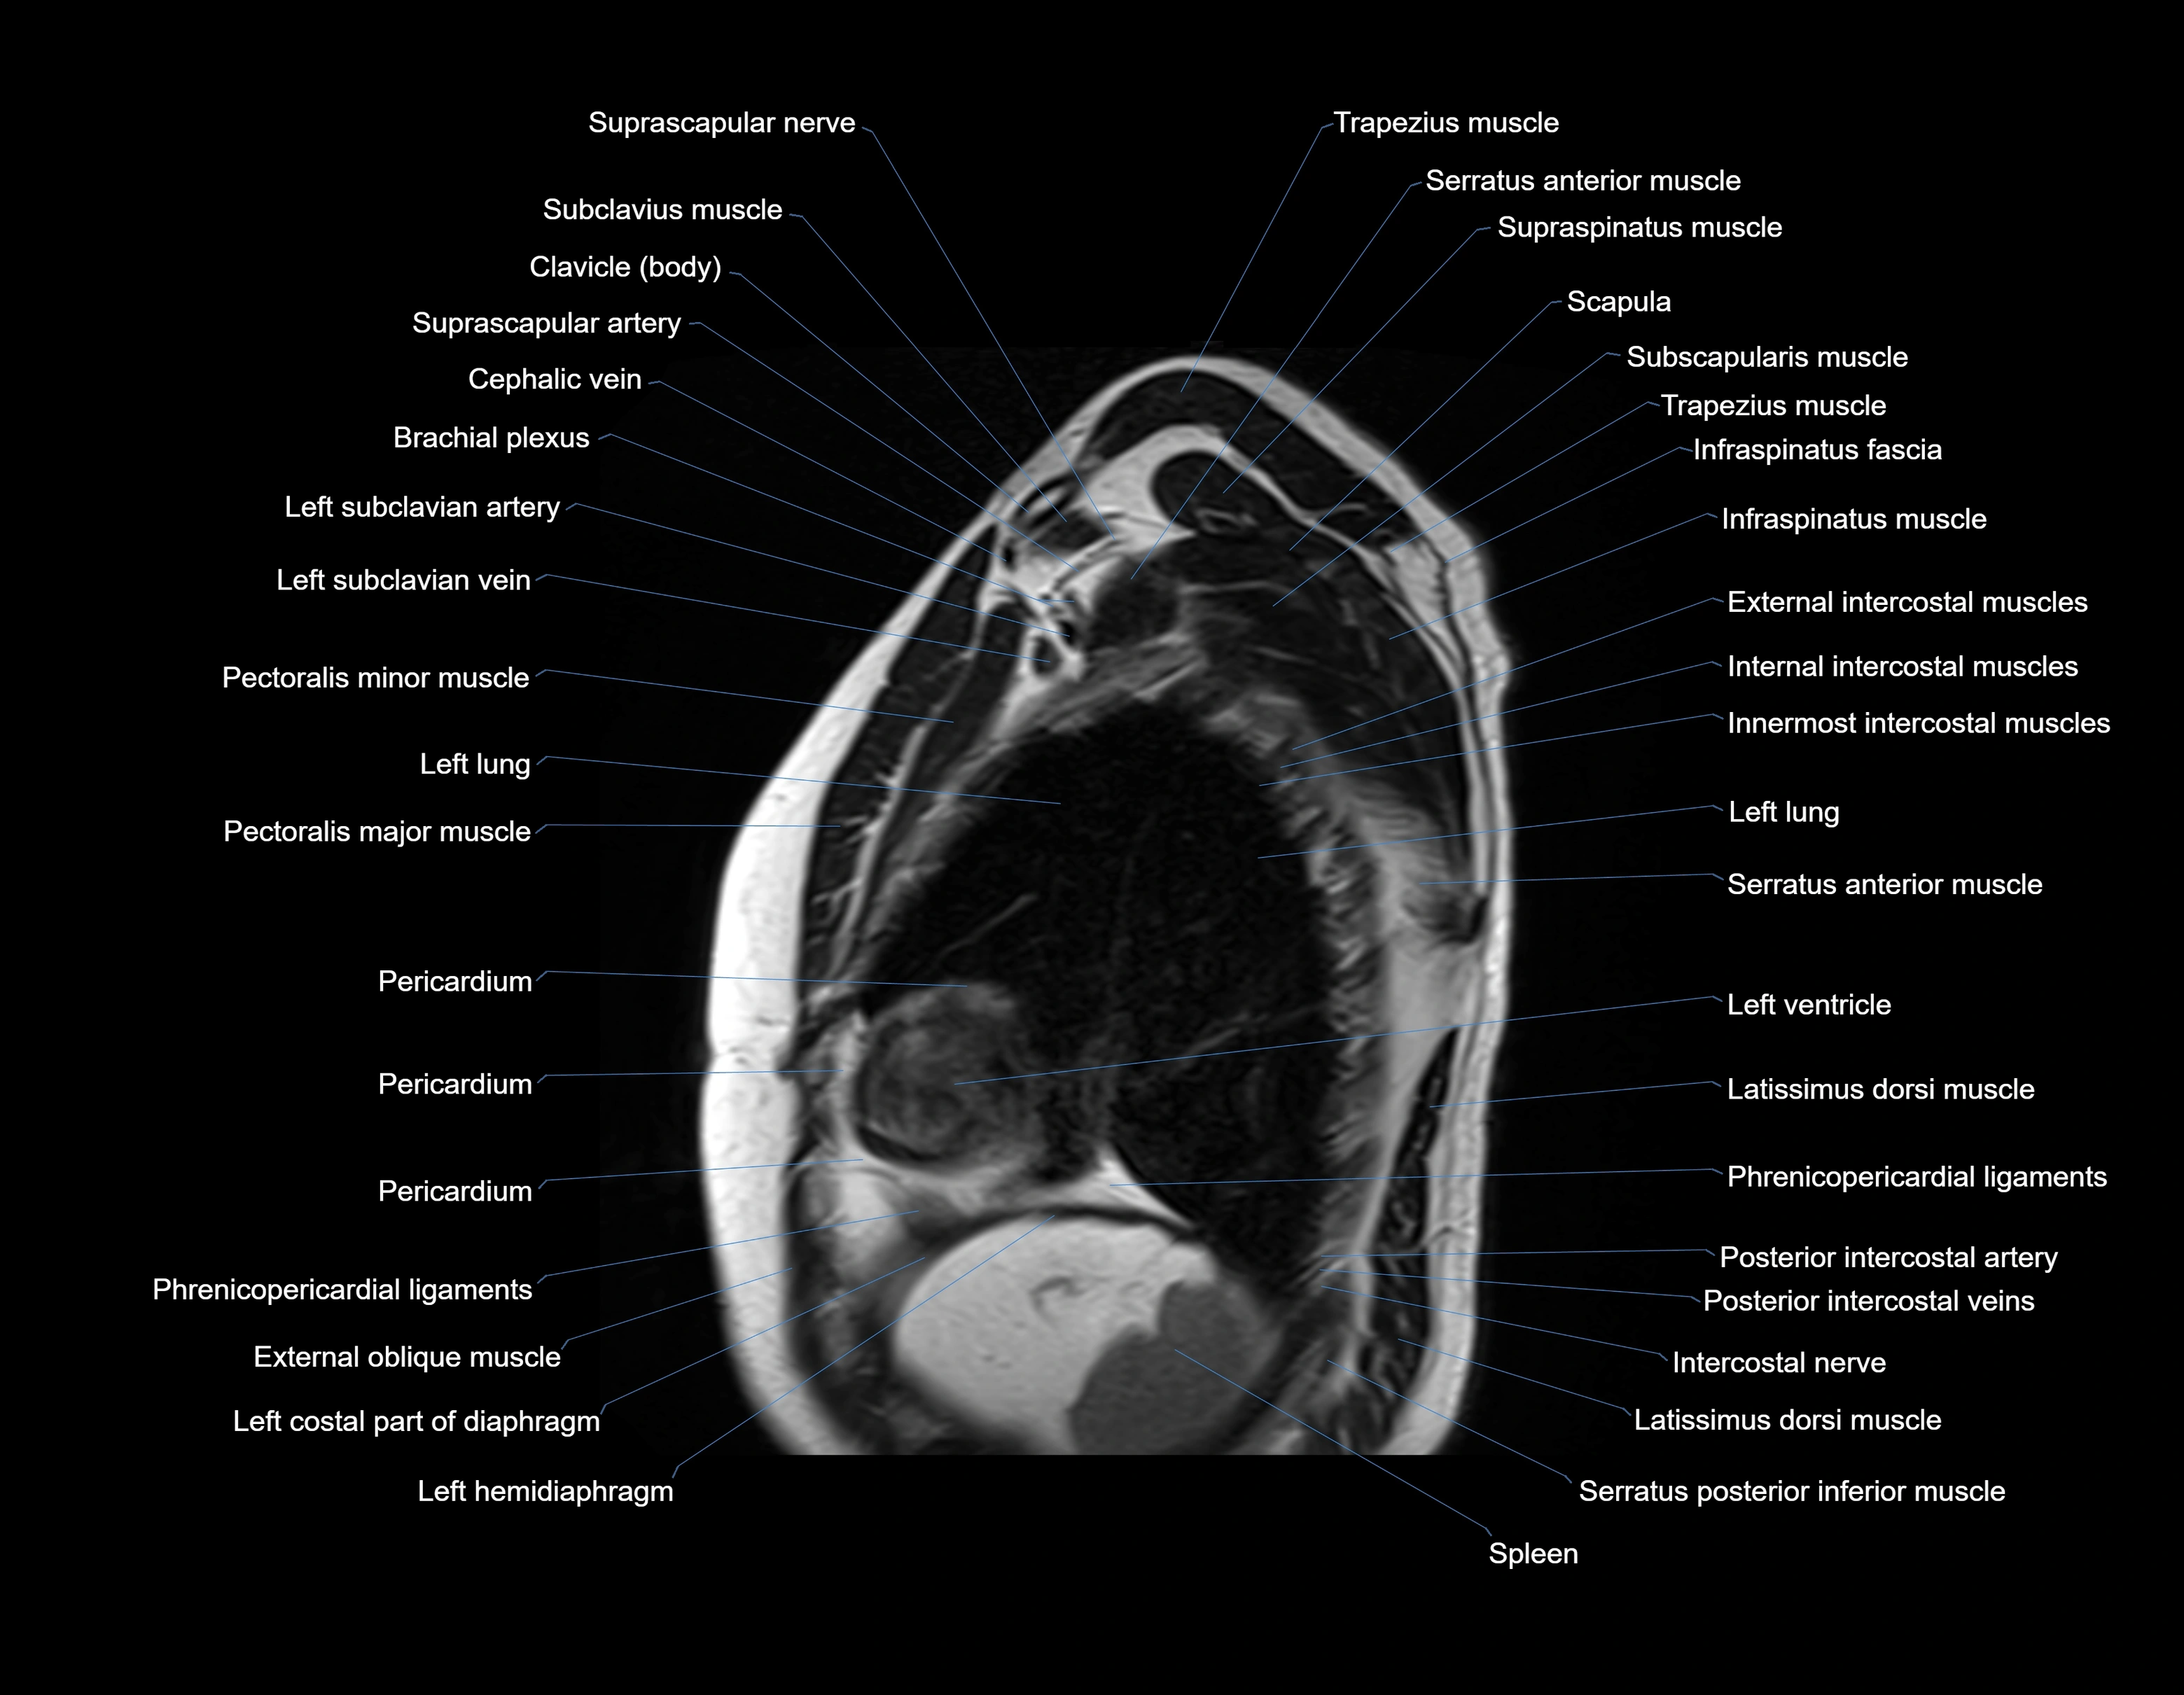

MRI images